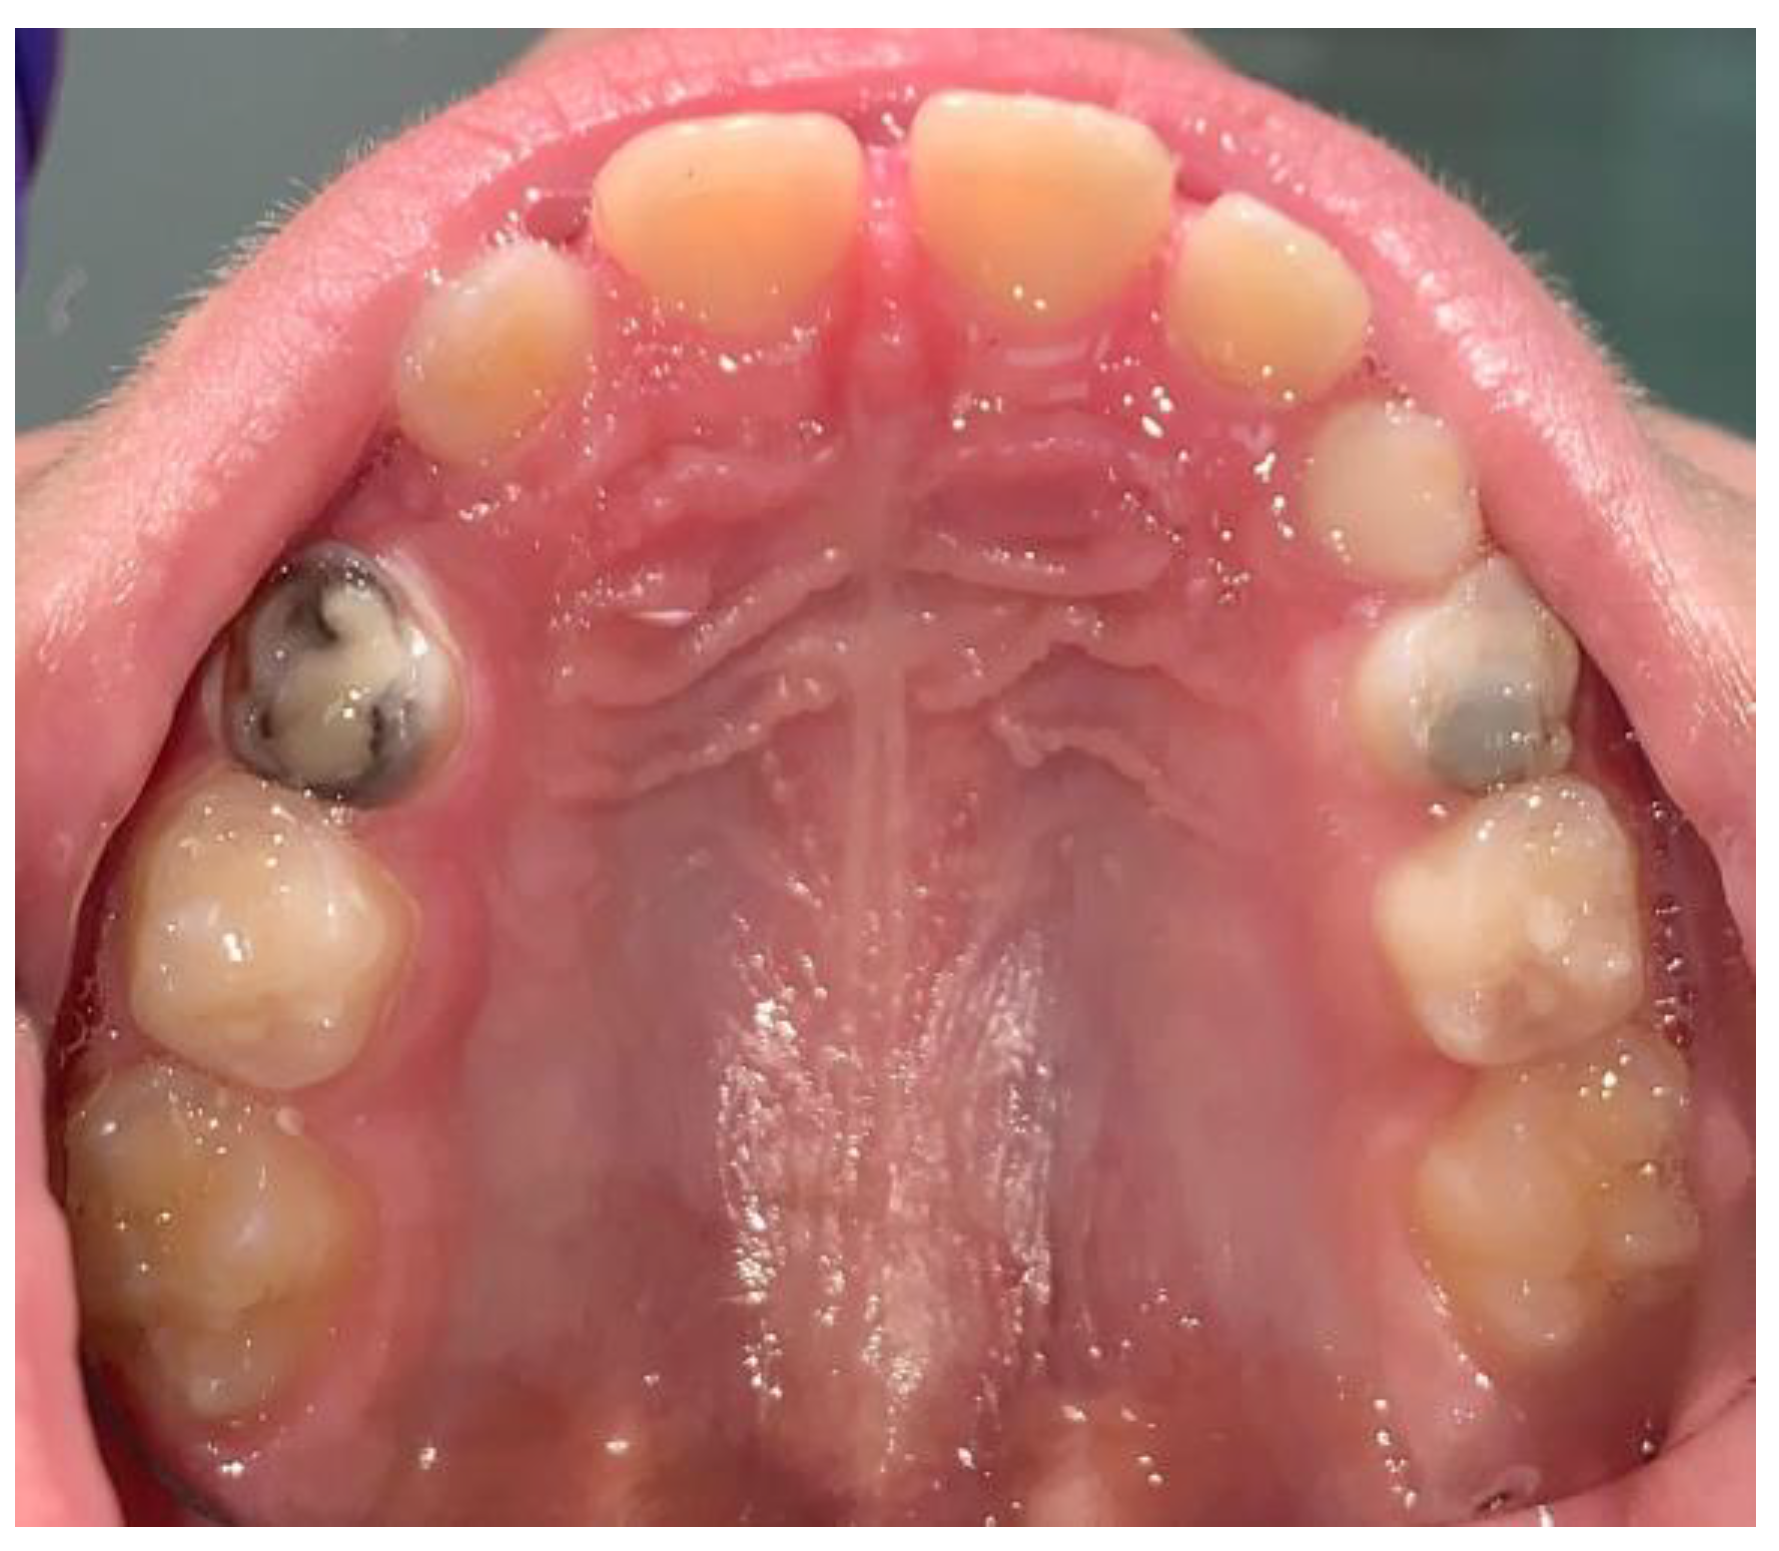

- Wambier, D.S.; Chibinski, A.C.R.; Wambier, L.M.; de Lima Navarro, M.F.; Banerjee, A. Minimum Intervention Oral Care Management of Early Childhood Caries: A 17-Year Follow-up Case Report. Eur. J. Paediatr. Dent. 2023, 24, 20–29. [Google Scholar] [CrossRef]